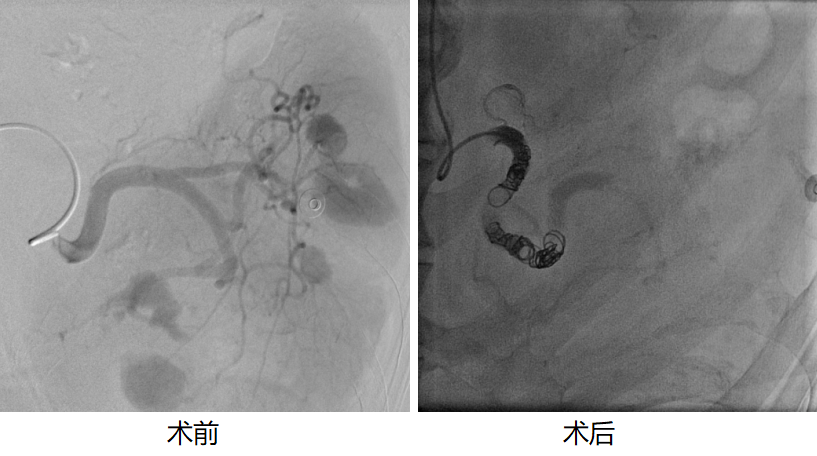

近日,延边大学附属医院(延边医院)肿瘤科联合介入诊疗中心,依托多学科协作(MDT)模式,成功为一名高龄脾破裂伴失血性休克前期患者成功实施脾动脉栓塞术。手术采用微创方式快速止血,有效保留了患者脾脏功能,降低了传统开腹手术相关风险,目前患者已顺利脱离生命危险。

肿瘤科主任朴龙镇团队联合介入诊疗中心在DSA设备精准引导下,经股动脉穿刺置入导管,插管至脾动脉主干,精准释放微型弹簧圈栓塞材料,通过降低脾动脉血流压力达到快速有效止血目的,同时最大限度保留健康脾组织及免疫功能。手术顺利完成,术后患者生命体征迅速稳定,腹痛明显缓解,复查提示出血完全停止,治疗效果理想。